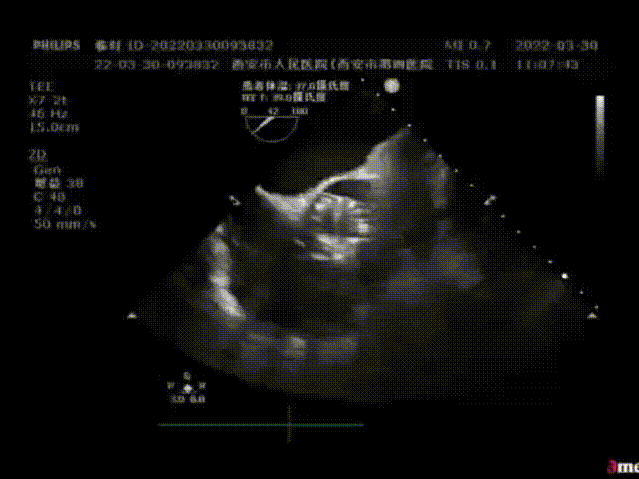

患者女性,主诉胸闷、气短3年,再发并加重3月,以“主动脉重度狭窄”入院,超声检查提示动脉瓣Vmax=4.2m/s,PGmax=71mmHg,瓣口面积约0.9cm²,诊断为主动脉瓣二叶畸形并重度狭窄。

植入前超声评估:瓣叶开闭不良

植入后超声评估:瓣膜形态良好,无瓣周漏